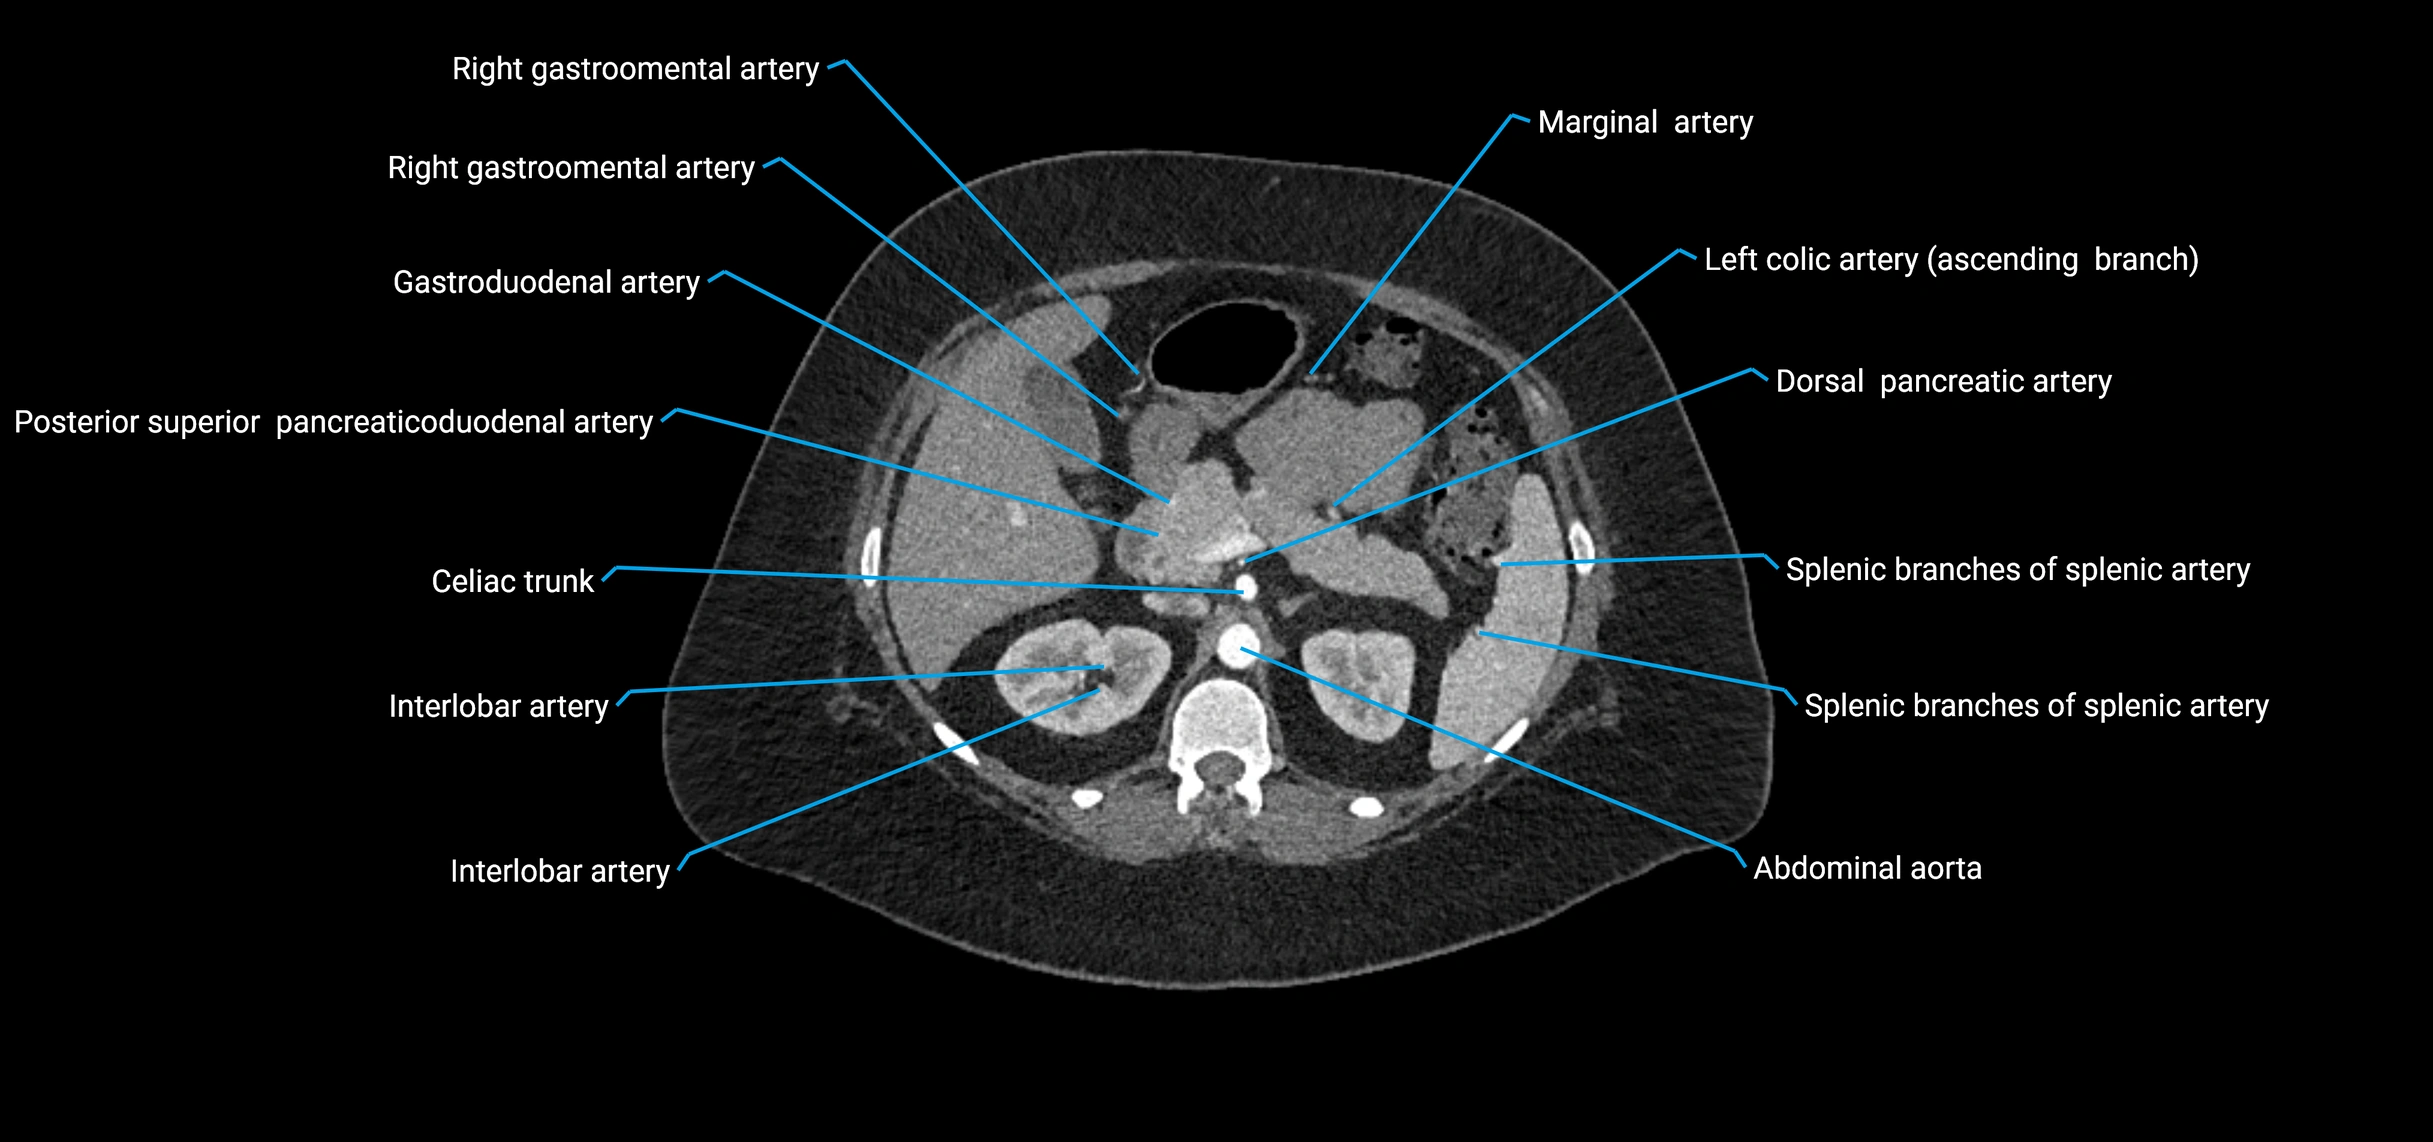

Contrast-enhanced CT (CTA):

• Gold standard for abdominal aortic imaging

• Provides excellent detail of lumen, wall, aneurysm, thrombus, and branch vessels

• Multiplanar and 3D reconstructions help in aneurysm measurement, stent graft planning, and dissection evaluation

• Detects acute rupture, traumatic injury, or occlusion with high sensitivity